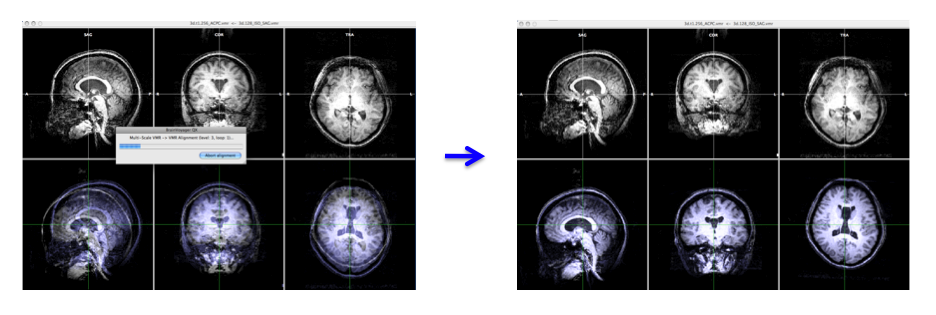

- In the "3D Volume Tools" dialogue, choose "Coregistration" and click "Select VMR..." button to select anat.low_SAG_ISO.vmr file for VMR-VMR coregistration.

Press "Align..." then "GO" in the "VMR-VMR Coregistration Options" dialogue. - Select "Spatial Transf" and click "Save .TRF" to save the parameter file for this spatial transformation.

-> You will get the anat.high_Man.trf file.